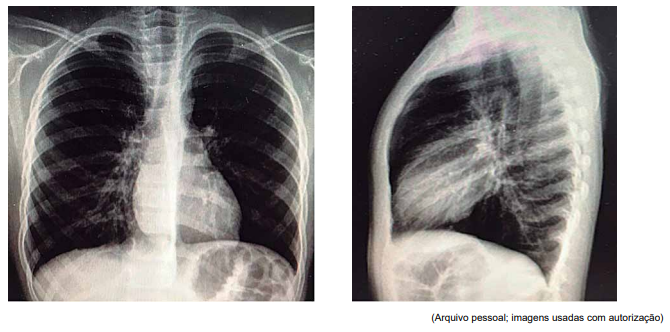

Paciente de 7 anos, com antecedente de asma de difícil controle, deu entrada no pronto-socorro com quadro de um dia de tosse seca e taquidispneia, sem febre. À admissão, encontrava-se em mau estado geral, com FR = 66 ipm; SatO2 = 85%, em ar ambiente, com sibilos inspiratórios e expiratórios à ausculta, com tiragens de fúrcula intercostal e subdiafragmática graves. Foram realizadas as radiografias de tórax a seguir.

Enunciado 4425055-1

Não houve resposta com as medidas adotadas, evoluindo com tórax silente e bradipneia, sendo indicada intubação. Foi transferido, então, à UTI pediátrica com os seguintes parâmetros ventilatórios: em pressão controlada (modo assistido- -controlado), com pressão positiva expiratória final (PEEP) = 8; frequência respiratória (FR) = 28 ipm; pressão inspiratória (Pinsp) (acima do PEEP) = 13; tempo inspiratório (Tins) = 0,7 s; fração inspirada de oxigênio (FiO2 ) = 100%, com assincronia ventilatória e saturação limítrofe.

Em face do exposto, assinale a alternativa que descreve, corretamente, os ajustes que devem ser realizados na ventilação.